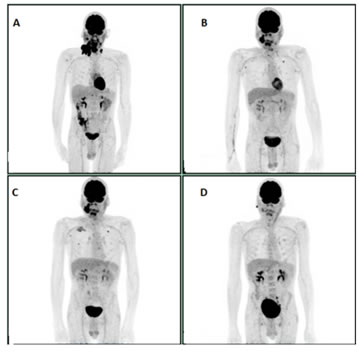

A 54-year-old white male with Stage IV A Squamous cell cancer of right tonsil P-16 positive (T2N2bM0) in August 2012. The patient was initially treated with concurrent chemo-radiation with Cisplatin 100 mg/M2 every three weeks. The patient completed chemo-radiation and was lost to follow up until 7/2014. PET scan done at that time showed no local disease. However, in the interim, he had developed an intense right hilar focus and biopsy of the hilar LN 12R on August 2014 confirmed Squamous cell carcinoma, basaloid type. On immune- histochemistry it was positive for P16 and P63 and negative for CD56 and synaptophysin. Given excellent performance status, he was started on Carboplatin (AUC 5 on day 1) and 5FU (1000 mg/m2 on day 1-4) with weekly Cetuximab (400 mg/m2 loading followed by 250 mg/m2) for two cycles. The PET scan post treatment on March 2015 showed sustained response in head and neck region, but persistent and slightly more prominent small subpleural nodularity in lateral right midlung concerning for new metastasis. He was started on Methotrexate which was continued until September 2016 and was stopped due to disease progression in the lungs. Immunotherapy with Pembrolizumab was started on on October 2016 and remained on it for a year. Patient progressed on Pembrolizumab after which he was switched to chemotherapy with weekly Paclitaxel and Cetuximab. The PET scan done after six cycles chemotherapy showed virtual complete metabolic response with minimally FDG avid lesions in right mid and lower lung field (Figure 2A-2D).

Figure 2: A: Initial study. B: PET scan prior to initiation of Pembrolizumab. C: PET scan after 4 cycles of Pembrolizumab showing progression. D: Virtual Complete response after 6 cycles of PC post Pembrolizumab progression.